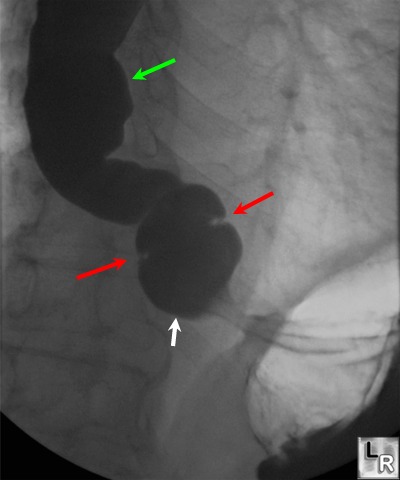

A schatzki ring is a circular membrane of mucosa and submucosa that forms at the squamocolumnar junction of the distal esophagus. Schatzki's ring is a narrowing of the lower part of the esophagus caused by changes in the esophageal mucosa (lining of the esophagus). Roy gt, cohen rc, williams sj. Ies of the esophagus,” in which he described. In 1953, schatzki and gary 1 described a thin luminal narrowing in the distal esophagus associated with dysphagia, that they called the lower esophageal ring .

In 1953, schatzki and gary 1 described a thin luminal narrowing in the distal esophagus associated with dysphagia, that they called the lower esophageal ring schatzki ring. Small hiatal hernias and rings.